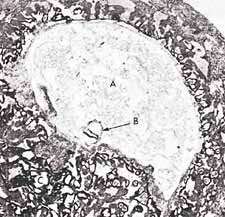

Суретке қарасақ “ғалақа” кезеңіндегі эмбрионның сыртқы пішіні сүлікке ұқсайтыны байқалады (бірінші суретке қараңыз). Сонымен қатар, осы кезеңдегі эмбрионның анасының қанымен қоректенетінін назарға алсақ, осы жөнінен де сүлікке ұқсастығы бар2.

(Рис. 1: На рисунке можно увидеть внешнее сходство пиявки и человеческого эмбриона на стадии алак . (Рисунок пиявки взят из книги Human Development as Described in the Quran and Sunnah, ["Развитие человека в трактовке Корана и Сунны"],Мур и другие (Moore and others), стр. 37, и представляет собой модифицированный вариант рисунка из книги Integrated Principles of Zoology ["Интегрированные принципы зоологии"], Хикман и другие (Hickman and others). Рисунок человеческого эмбриона взят из книги The Developing Human ["Развивающися человек"], Мур (Moore) и Персо (Persaud), 5-е издание, стр. 73.).

(Рис. 3: На этой микрофотографии мы можем видеть, как на стадии алак эмбрион в возрасте 15 дней (отмечен буквой В) подвешен в утробе матери. Истинный размер этого эмбриона - около 0,6 мм.(Рисунок взят из книги The Developing Human ["Развивающися человек"], Мур (Moore), 3-е издание,стр. 66, и воспроизводит рисунок из книги Histology ["Гистология"] Лисон и Лисон (Leeson and Leeson))